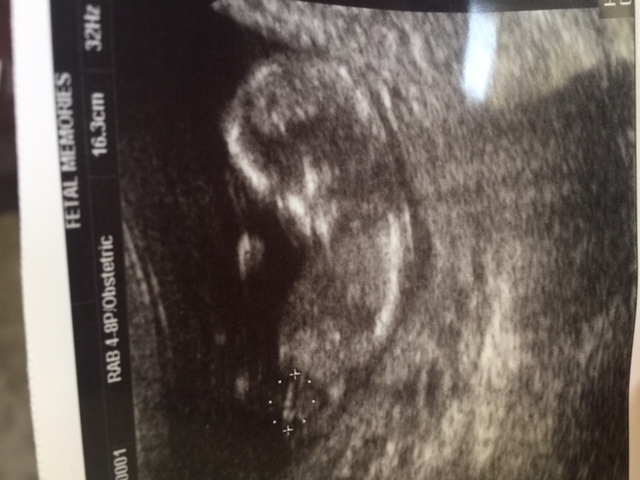

13 weeks + 1 day. Doctor said 95% chance girl. We prefer a boy. Are there any possibility to be a boy later on? Would it be too early to tell the gender?

Looking extremely girly but a boy is not impossible, ultrasound is not 100% especially at this stage.